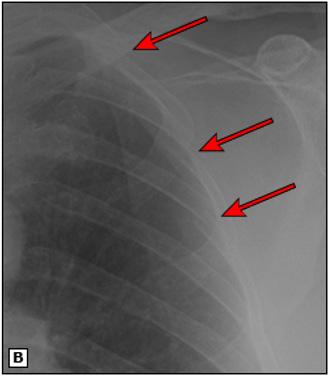

Figura 37. La radiografía portátil AP de tórax (imagen A y ampliada en la imagen B) revela fracturas agudas de las caras laterales de las costillas 2, 3 y 4 del lado izquierdo (flechas rojas) después de un traumatismo.